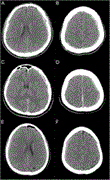

Supratentorial acute subdural haematoma during microvascular decompression surgery: report of three cases

Kenichi Amagasaki and others

Journal of Surgical Case Reports, Volume 2017, Issue 2, February 2017, rjx004, https://doi.org/10.1093/jscr/rjx004